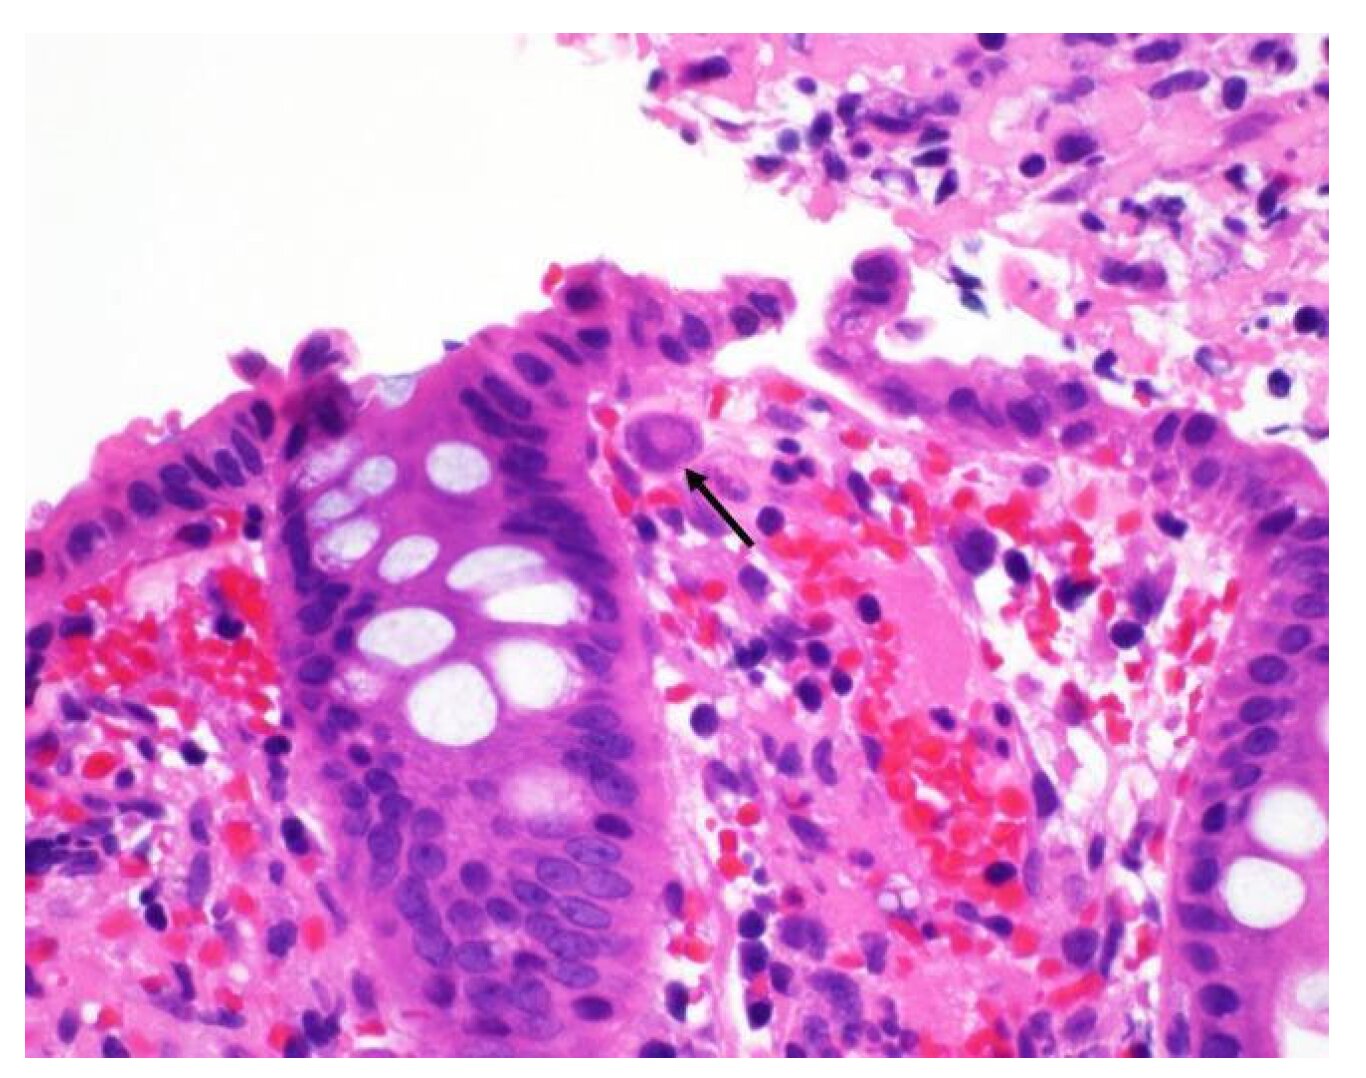

Lorsque le CMV réactive, il peut impliquer le côlon, en particulier chez les patients atteints de MII. Cette forme d’infection à CMV, connue sous le nom de colite CMV, est fréquemment sous-reconnue ou mal diagnostiquée, selon Alfredo Puing de la Yale School of Medicine, MD, qui note que les symptômes de la colite CMV, tels que les douleurs abdominales et la fièvre, imitent souvent une éruption de MII.